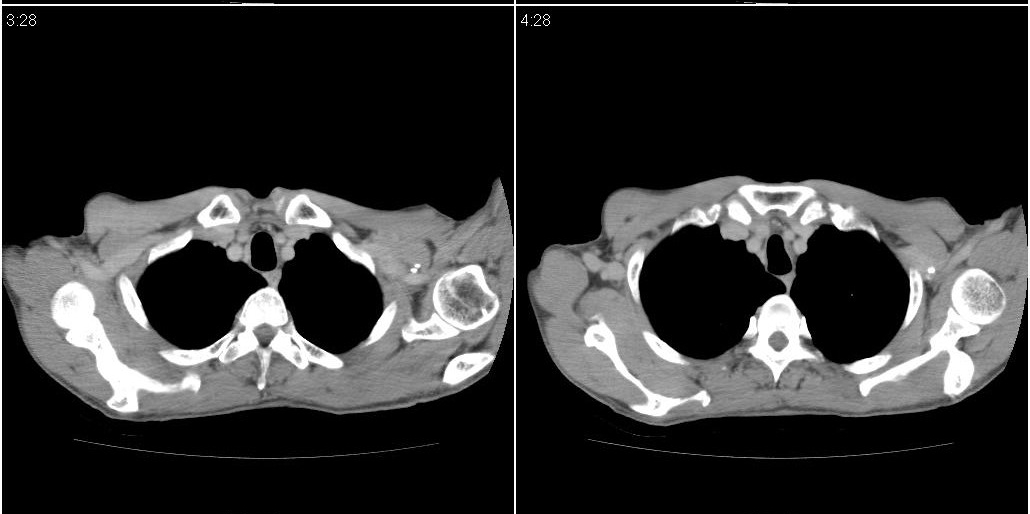

以下是ct检查的情况:

考虑右肺下叶炎症可能性大?未除占位,建议增强。右下肺肺不张

右下肺阻塞性肺炎!建议纤支镜!

右肺中叶阻塞性不张及肺炎,高度怀疑支气管占位,建议纤支镜检查!

1)右肺中叶慢性炎症并支气管扩张,节段性肺不张。2)两肺下叶支气管扩张。